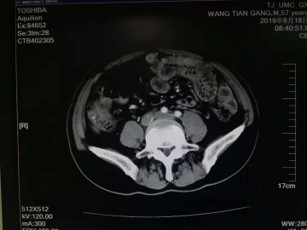

2019.6.18复查

全腹及胸强化CT示:1.左半结肠切除术后改变,吻合口区及保留结直肠未见明显异常;2.右侧心隔角、腹盆腔腹膜及腹膜后多发转移性病变,较前(2019.2.26)未见明显变化。